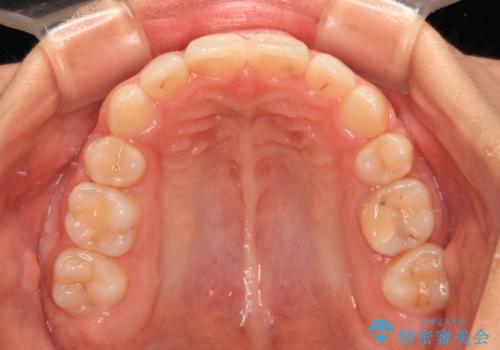

補助装置を併用したおかげでスムーズに奥歯の咬み合わせを改善することができ、我々も予想できないくらい理想的な仕上がりにすることができました。